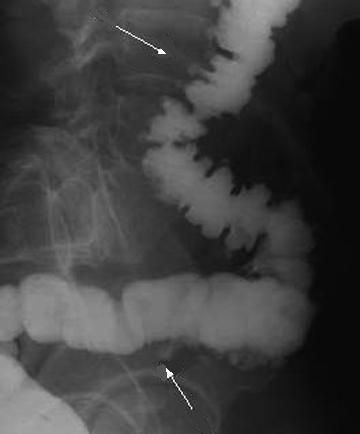

- Image

radiologique de diverticule du colon descendant et

une partie du colon transverse . Les diverticule en

face se donne une image resemble des polyps, ce

qu'il peut elimine par la reste de baryte dans le

sac de diverticule . Lavement baryte en double de

contrast . |

- Aspect des diverticules du colon

sigmoide sur le lavement baryte en

double de contrast . Image de reste de baryte dans

les diverticules en se voyaient si nette . |